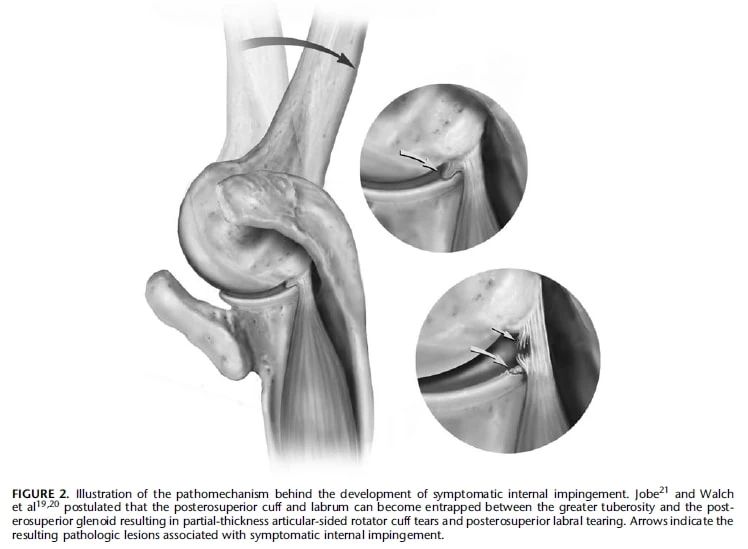

肩关节内撞击是指肩部肩袖和关节囊的软组织在盂骨(肩胛骨的一部分)和肱骨(上臂骨)之间受到挤压或压迫时出现的一组症状。 这通常发生在肩部处于特定位置时,如外展(远离身体)和外旋(向外翻转)。 它不同于外部撞击,在外部撞击中,袖带和滑囊会挤压到肩峰弓的结构。 内撞击的确切原因仍有争议,但它似乎是某些肩部姿势下的正常现象。 内撞击的影像学检查结果可能包括袖带部分厚度撕裂、唇瓣病变和骨质变化。

内撞击综合征有两种类型:后上方撞击和前上方(前方)撞击。 当靠近冈上肌腱和冈下肌腱交界处的肩袖后上部与盂后上部接触时,就会发生后上部内撞击。 而前上撞击则是指前肩袖与前上盂之间的撞击。 这些病症的特点是肩袖软组织和关节囊撞击到盂上或盂与肱骨之间。